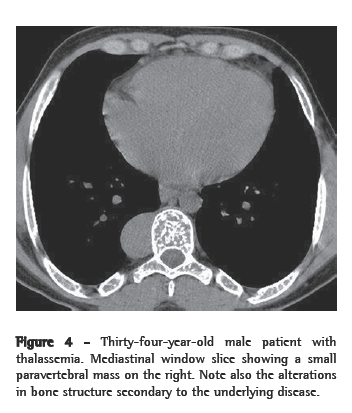

The remaining two patients each presented a parietal pleural mass, both on the left, with no evidence of paravertebral involvement. In one of them, the mass was homogeneous (Figures 3a and 3b), and, in the other, there was associated bone reaction.

As associated findings, two patients presented calcifications in the spleen (Figure 4). Both of them had sickle cell anemia. Two of the six patients had undergone splenectomy, and two presented normal spleen imaging findings. Bone alterations related to the underlying disease were identified in three patients.

On CT scans, masses with dense soft parts, usually homogeneous, with characteristics similar to those described using conventional radiology,(1,2,5,6) and which might or might not be highlighted after administration of contrast material,(4,10) can be seen. This imaging method is important for analyzing the internal structure of the lesions, especially of those that are rich in fat,(5) in order to identify other paracostal masses, and for detecting bone alterations associated with certain hematologic diseases, such as thalassemia and sickle cell anemia.(6) In cases related to thalassemia, sickle cell anemia, or myeloid metaplasia, there can be widening of the medullary cavities of the ribs.(5) All of those aspects were identified in our cases. It is of note that two patients presented calcifications in the spleen, resulting from multiple infarcts, with autosplenectomy. Both of those patients had sickle cell anemia. This finding can also facilitate the differential diagnosis.